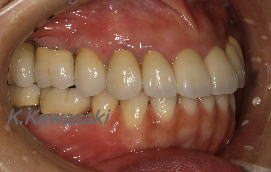

| 前歯の作り直しを希望して来院されました。このままでは受け口の状態か、前歯を出っ歯にして作り直すしかありません。 |

部分矯正で下の歯を引っ込めた後セラミックで作り直しました。 |

横から見ても受け口が治り自然な感じになりました。